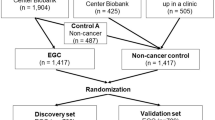

In order to prospectively examine the circulating miRNA signature, serum specimens were collected from 178 patients with ESCC and 195 healthy individuals, matched by age and sex, who were prospectively recruited from February to July 2018 at the National Cancer Center/National Clinical Research Center for Cancer/Cancer Hospital, Chinese Academy of Medical Sciences, Beijing, China (Table 1). qPCR quantification was performed on the Beijing-1 cohort (89 ESCC vs. 96 healthy). The data generated from the Beijing-1 cohort was used to train a multivariate logistic regression model and establish an ESCC risk-scoring formula. The performance of the circulating miRNA signature was subsequently evaluated based on qPCR data from the Beijing-2 cohort (89 ESCC vs 99 healthy).

Validation of the diagnostic performance of the circulating miRNA signature in two, independent, prospective cohorts of ESCC patients

To demonstrate the clinical application of our circulating miRNA signature in true clinical settings, we next examined its performance in two, randomized, prospectively enrolled patient cohorts. We performed qRT-PCR assays to assess the expression of the 8-miRNAs signature in 186 serum specimens (Beijing-1 cohort; 84 ESCC patients and 102 healthy controls) and used this cohort as our training set. We performed multivariate logistic regression analysis and derived a risk-scoring formula: logit(P) = (0.00810 x miR17)–(0.183 x miR21)–(0.974 x miR25) + (0.973 x miR93)–(0.347 x miR103)–(0.298 x miR106b)-(0.194 x miR151) + (0.226 x miR181a)-3.196. Our 8-miRNA signature performed robustly in its ability to distinguish ESCC patients from healthy controls (Fig. 4A, S10A, S11A, AUC = 0.92, 95% CI: 0.87–0.96, sensitivity: 89%, specificity: 84%). Subsequently, we assessed the performance of this miRNA signature in an independent validation cohort (Beijing-2 cohort; 89 ESCC patients and 99 healthy controls). Once again, our signature robustly distinguished ESCC patients from healthy controls (Fig. 4B, S10B, S11B, S12, AUC = 0.93, 95% CI: 0.88–0.97, sensitivity: 93%, specificity: 89%; Table S6). In both training and validation cohorts, our 8-miRNA signature performed substantially better than individual miRNAs in identifying ESCC patients (S11A and S11B).